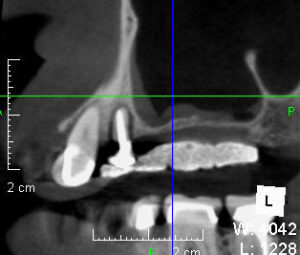

インプラント

Case Studies